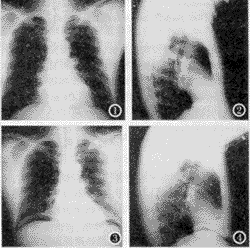

病例 男性,52岁,X线检查发现左侧心膈角肿物有4cm×4cm大小,椭圆形,正位肿物与心影重叠,侧位肿物位于膈肌上、下几乎各占一半,上半部与膈肌阴影融合,下半部分(膈下部分)轮廓清晰可见(图1、2)。人工气腹后,诊断为膈肌肿瘤(图3、4)。术后证实为膈肌纤维瘤。

图1 正位胸片,左心膈角区见一4cm×4cm肿块,边界清楚。

图2 左侧位胸片,该病灶位于左膈顶处,部分与心影相叠。

图3 人工气腹正位片,见膈肌肿瘤与人影重叠。

图4 人工气腹侧位片,膈肌肿瘤呈倾斜椭圆形。